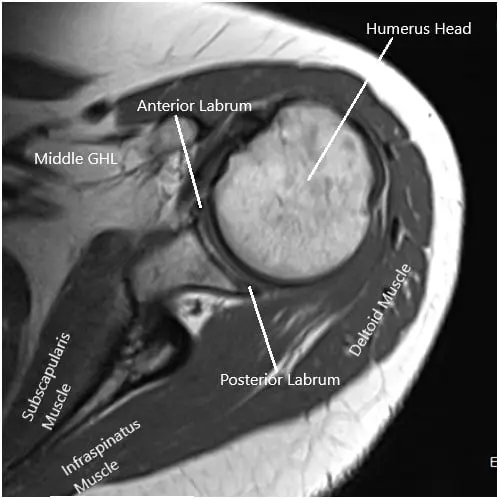

MRI of the left shoulder suggested tendinosis of the supraspinatus tendon with a partial articular surface tear of the anterior and mid substance fibers of the tendon. Tendinosis of the infraspinatus tendon. Subacromial/subdeltoid bursal fluid reflecting bursitis. Degeneration and tear of the anterosuperior labrum.

MRI image of the shoulder in axial and coronal sections